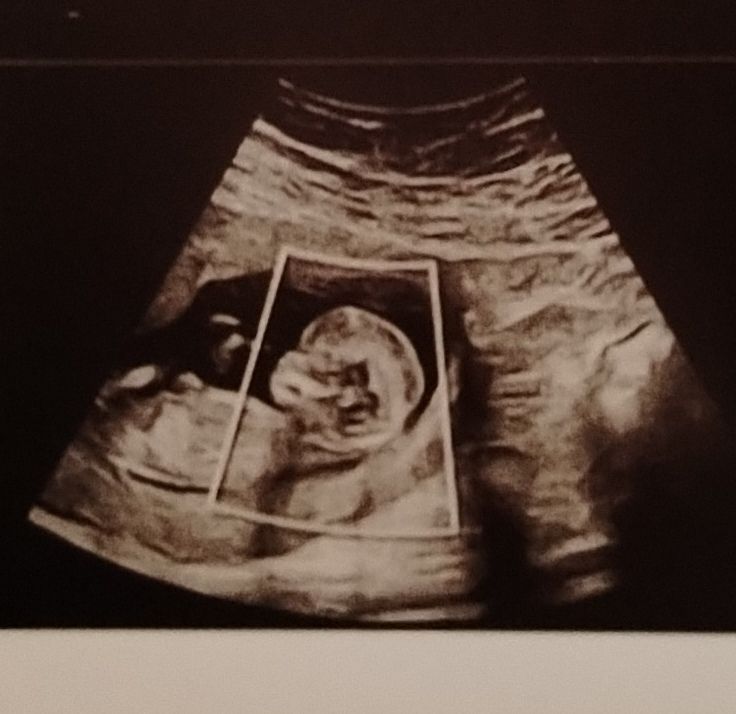

Тоже недавно совсем мониторила по скринингу какой пол у малыша может быть) так похоже на девочку ) и мне подтвердили , у меня кстати похоже фото скрининга ) Вроде если мальчик то бугорок смотрит выше Изображение

Katrinrina, да, больше на девочку похож, но я видела у одной женщины точно такое же узи как у вас и у меня, и у нее был мальчик, на 20 неделе подтвердили ей, так что жду тоже этого срока, чтобы быть точно уверенной в поле будущего малыша ))

Eva , мне как раз на 20 сказали девочка, на 12 я сама себе подтвердила и еще мужу радостно написала , что я знаю кто будет) Интересно как у автора будет)

Katrinrina, сама жду не дождусь 20й недели, без разницы кто будет, главное точно узнать😂 но сам узист очень опытный, 11 лет работы, новейший аппарат, но она и то сама дала лишь 60-70% правдивость результата. но я думаю, что она не ошиблась))

Eva , можете и на 15 сходить, там уже более точно будет ))